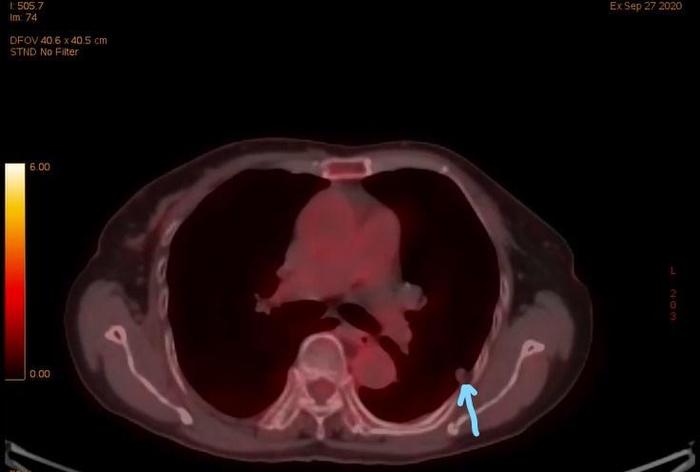

有一个老太太,2018年3月发现左下肺一个混合磨玻璃结节,当地医院和南京市的**医院两年来一直考虑是良性的。

两年期间曾经静脉抗炎,结节无变化。

今年终于有医生怀疑可能是恶性的,进行了肺穿刺检查,证实是肺腺癌。其实如果看CT片水平高,两年半前就可以看出是肺癌。病人后来到我这儿住院,病人较矮小,体型类似于大龄儿童,体重极低,还曾经有过脊柱压缩性骨折。围手术期风险很大。